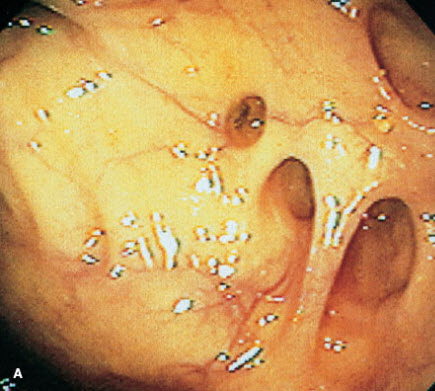

Extensive diverticulosis was found throughout the length of the colon of an 84-year-old woman, who depended on a weekly dose of magnesium citrate to have a bowel movement. Typical lesions are shown here (A and B). Diverticula may occur singly or clustered in small groups, with narrow or broad openings into the colonic lumen.

Diverticulosis rarely affects persons under age 40; however, its incidence increases dramatically with each succeeding decade. Although patients with this disorder are frequently asymptomatic, abdominal cramps, constipation, and flatulence may mark the presence of the disease.